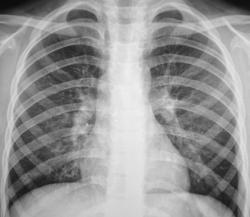

После цифровой обработки изображения и увеличения его (иллюстрации 2, 3, 4) медио – базально определяются округлой, каплевидной и неправильной формы просветления, по всей видимости бронхоэктазы дизонтогенетического генеза.

Вокруг бронхоэктазов определяется снижение прозрачности легочной ткани.